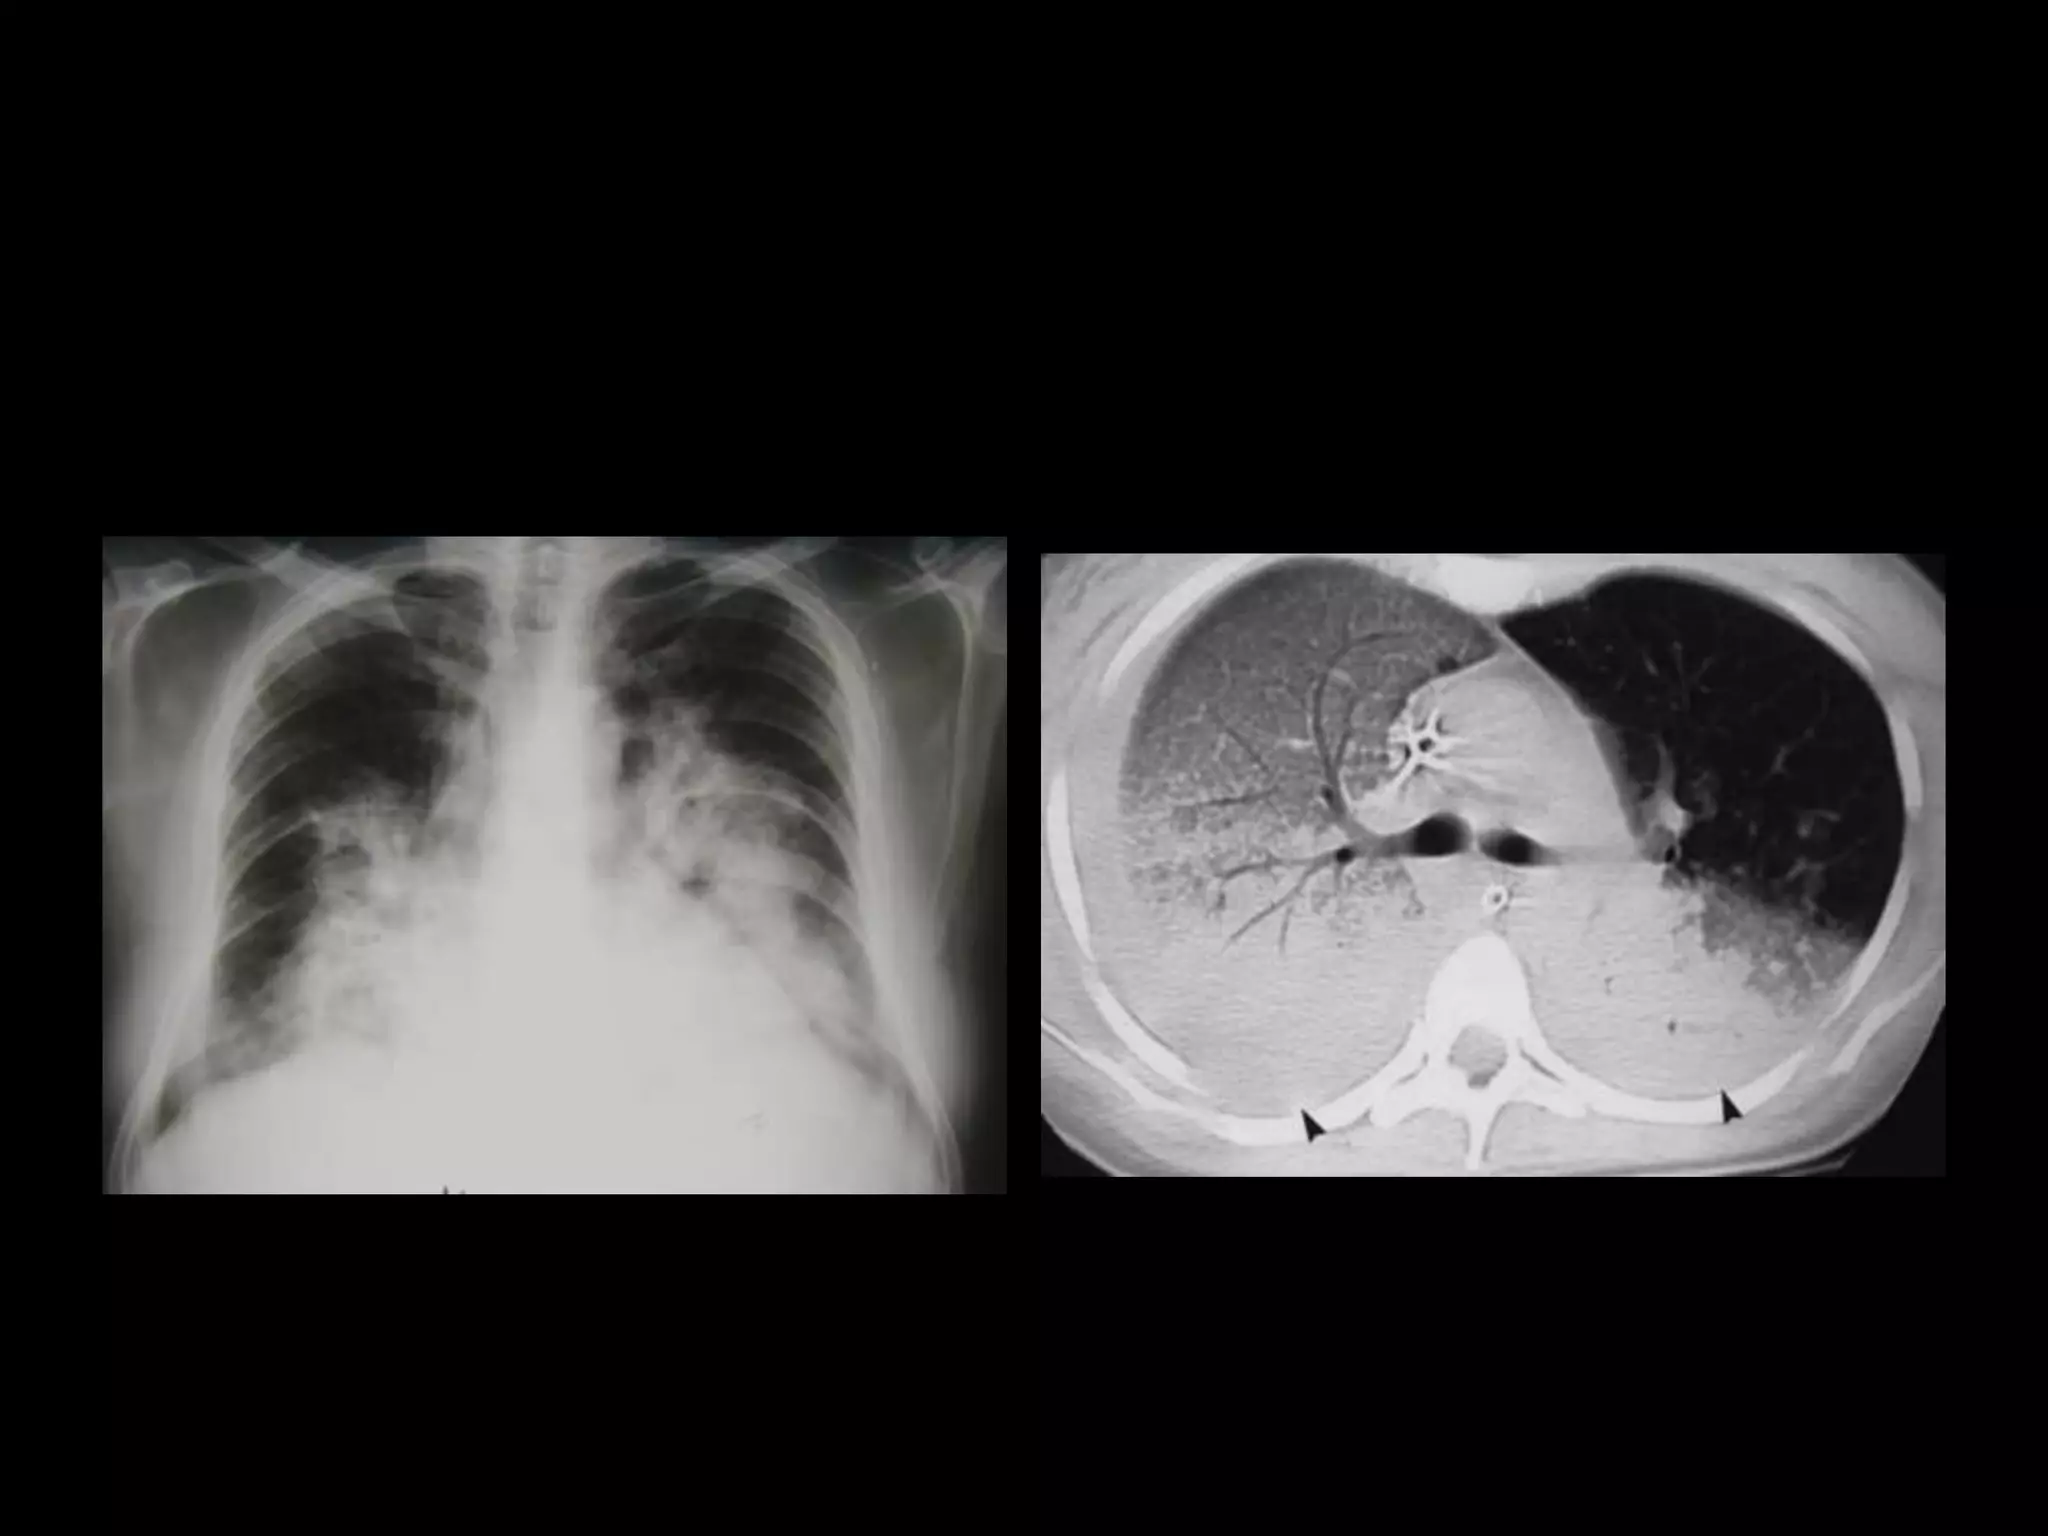

Este documento proporciona una lista de términos radiológicos relacionados con el tórax y los pulmones. Incluye descripciones breves de diferentes patrones de opacidad pulmonar como consolidación, neumotorax, nódulos y cavernas, así como sus posibles causas. También cubre términos relacionados con el mediastino y las técnicas de imagen torácica.